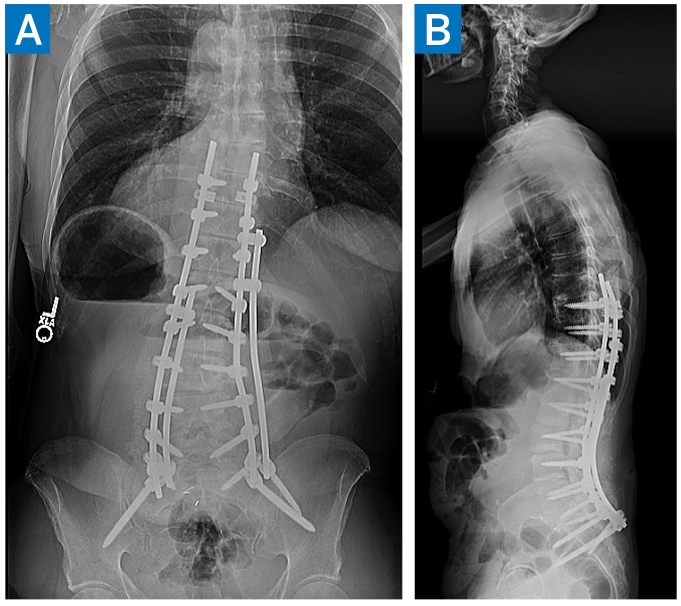

An enhanced recovery pathway [3] was enacted, and the patient was discharged home on postoperative day 4. At 6-week follow up, he said he could walk nearly 20 blocks and stand up for more than 10 minutes, the best he had achieved in years. At 3-month follow up, he noted minimal back pain and was comfortably taking long walks outdoors. X-rays demonstrated maintained alignment (Fig. 2).

Figure 2: 3-month postoperative AP (A) and lateral (B) X-rays demonstrating maintained deformity correction.